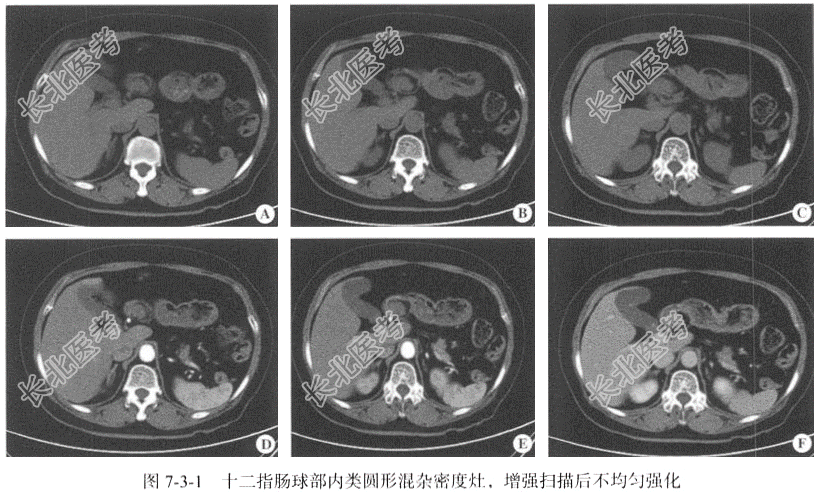

【影像图片】见图7-3-1。

【手术所见】肿物位于十二指肠球部,来源于黏膜下层,未浸透浆膜,游离度良好,大小约为4.00cm×3.00cm,质软,油腻。

【病理所见】肉眼所见(十二指肠肿瘤)不整组织2块,大小为6.50cm×2.50cm×2.00cm,表面呈灰红色、灰黄色,切面呈灰黄色,质软,油腻(图7-3-2)。免疫组化结果:AE1/AE3(+),Ki-67(2%+)。

【病理诊断】十二指肠肠腺腺瘤。